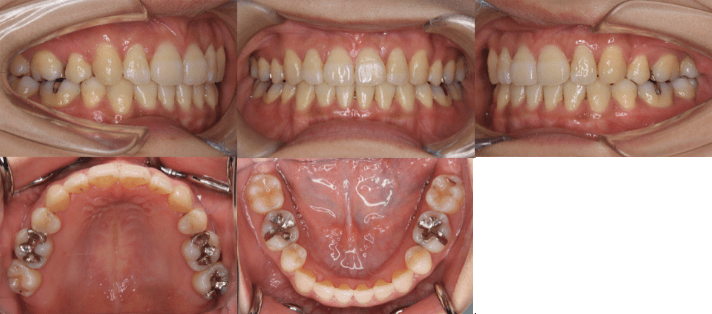

<治療前>

<治療後>

初診時年齢 25歳7ヶ月

主訴 前歯のガタガタ

診断 交叉咬合を伴う叢生症例

治療内容 小臼歯4本を抜歯した後、インビザラインを使用して主訴である叢生の改善を行いました。

治療期間 2年

リスク 矯正治療による歯の移動に伴う痛み、歯根吸収、虫歯

費用 80万円